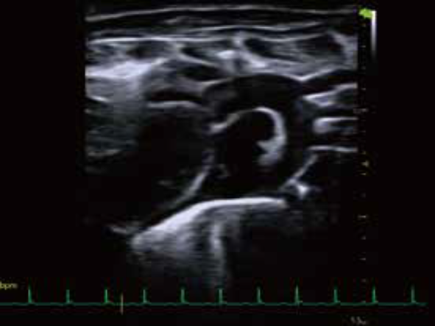

• マウス大動脈弓Bモード画像

D10 LAB は高い時空間解像度30μm, 500fpsを可能にしたポータブルタイプの超音波イメージングシステムのハイエンドモデルです。 ポータブルタイプでは世界トップクラスの性能を有し, マウス心機能の解析や小動物の体内を繊細に観察・測定できます。